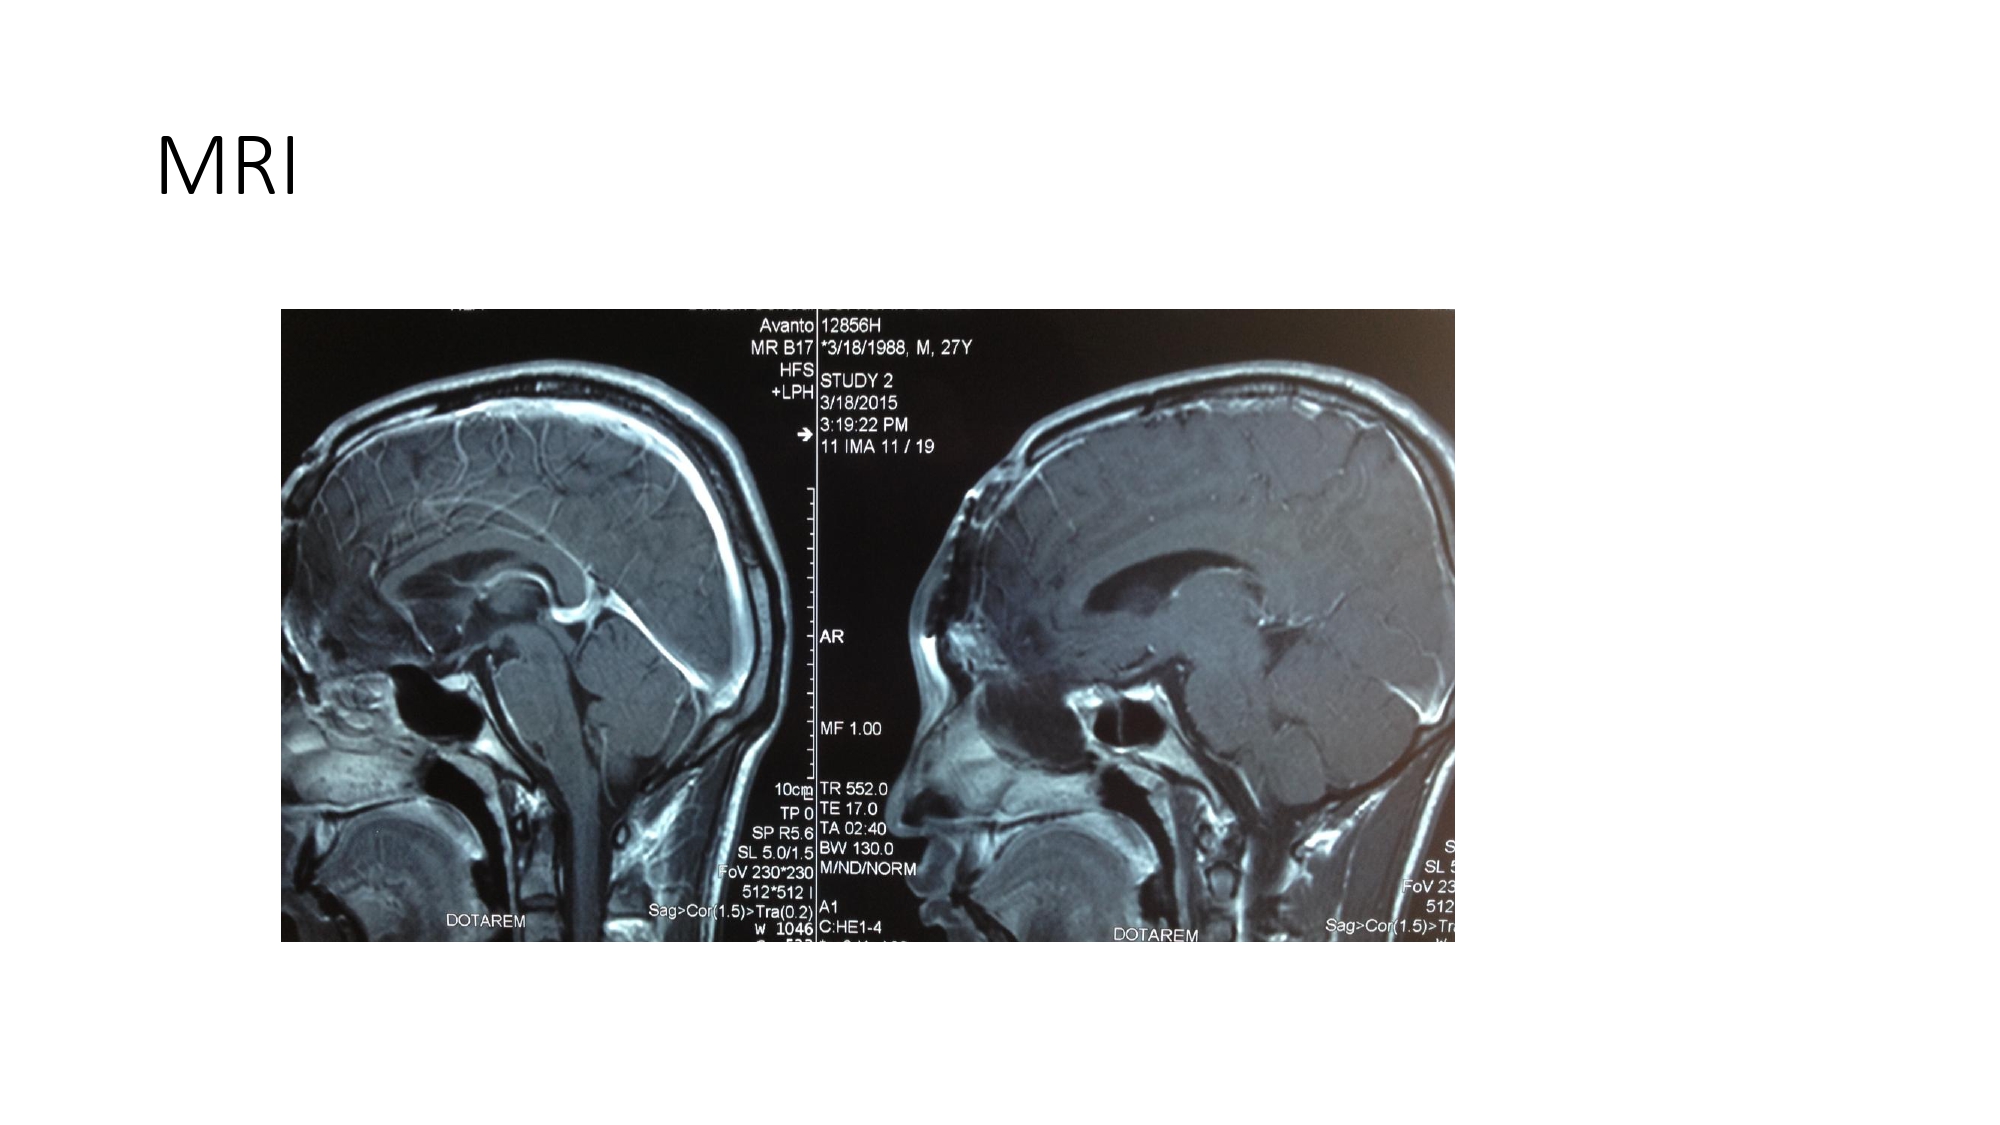

| 08:40 - 09:20 | Diagnosis of skull base trauma Post-traumatic CSF leakage | Assoc. Prof. Dong Van He Assoc. Prof. Kieu Dinh Hung | |

| 11:05 - 12:00 | Interactive Case Demonstration and Discussion I ~20 minutes each, (5 minutes presentation followed by 15 minutes discussion) Practicals: How I am doing it? Participants present case presentations about how they do it? The faculty comment on and discussion. 1. ICP management: How I am doing it? - Assoc. Prof. Duong Dai Ha 2. CSF leakage management: How I am doing it? - Assoc. Prof. Nguyen Thanh Bac | Prof. Christian Matula International & local faculties Participants | |